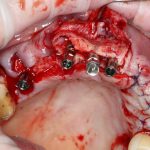

Итак, Зинаида на приеме.

Вот клиническая картина через 4 месяца после ранее проведенной имплантации с остеопластикой:

Как видишь, коллеги из недалекой дружественной страны не осилили снятие швов. Мне это не нравится, хотя и объясняет, почему люди готовы ехать за тыщи километров ради 20-минутной операции удаления зуба мудрости.

Ну хорошо. Швы сняли. Делаем разрез. Обрати внимание, что после всех проведенных операций у нас остается очень небольшой по ширине слой жевательной слизистой оболочки:

Устанавливаем формирователи десневой манжеты. Сегодня я называю эту процедуру не менее важной, чем любой другой этап имплантологического лечения:

И швы. Просто швы. Никаких дополнительных процедур.